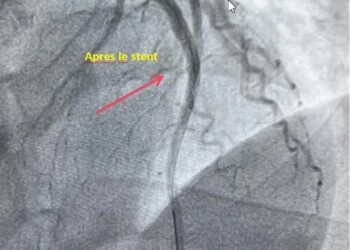

Dans le cadre de la prise en charge d’un infarctus aigu du myocarde localisé sur la paroi antérieure, une coronarographie ...